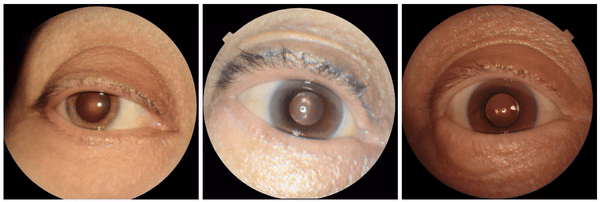

Positive controls

First, to ensure the framework successfully identifies known visual attributes, we examined tasks for each imaging modality, where some known attributes exist (i.e., “positive control” experiments). Indeed, we found that cortical cataract spokes were seen for cataract prediction from external eye photos, retinal vein dilation for smoking status prediction from fundus photos, and left ventricular enlargement for abnormality prediction from CXRs.

StylEx-0-Hero

Examples of “known” (positive control) attributes extracted by our approach: a) Spokes for cataract presence, which appear as radial opacities like spokes of a wheel; b) retinal vein dilation for smoking status; c) left ventricular enlargement for abnormal CXR.